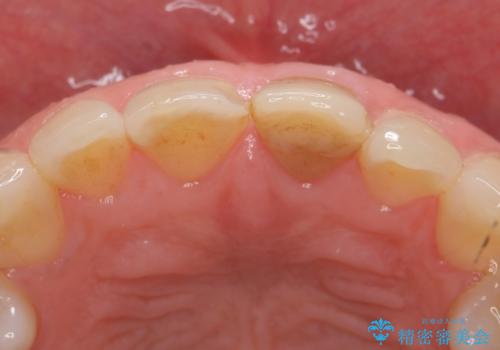

- 前歯の変色が気になるのでセラミックによる治療を行いたいといらっしゃった方の症例です。

左上1番目の歯の再根管治療終了後、左右1番目の2歯をオールセラミッククラウンで補綴しました。

- オールセラミッククラウン…¥100,000×2、仮歯…¥10,000×2、ファイバーコア…¥20,000費用は治療当時の料金となります